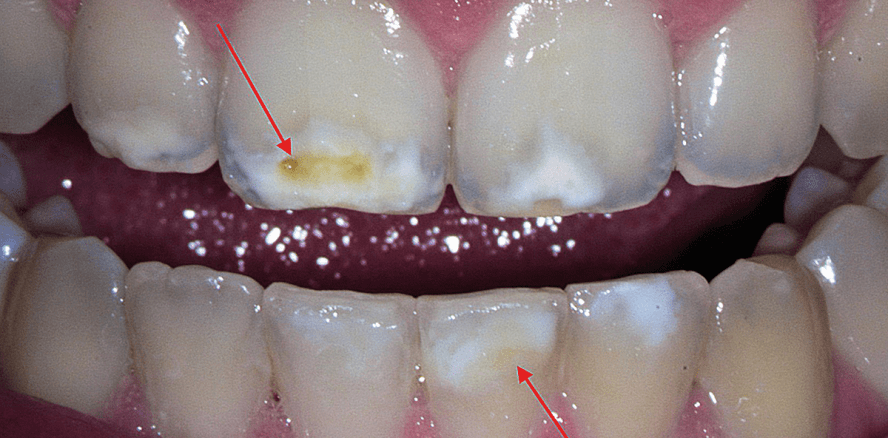

Bei der Inspektion der Mundhöhle fielen als erstes abgegrenzte Opazitäten an den permanenten Inzisivi (PI) auf (Abb. 1). Dabei weisen die Zähne 12, 21, 32, 31, 41 eine milde Form der MIH mit weißlichen Opazitäten auf. Die abgegrenzten Areale sind auf den labialen Glattflächen zu diagnostizieren. Bei 31 ist zudem ein Übergang von der Labialfläche hin zur Inzisalfläche und ein gelblicher Schimmer in der weißen Opazität zu verzeichnen. Der Zahn 11 zeigt größere opake Defekte im inzisalen Drittel auf. Dabei sind weißliche als auch abgegrenzte gelb-bräunliche Defekte zu erkennen. Dies weist auf die moderate Form der MIH hin. Keiner der betroffenen PI wies gesteigerte Sensibilitäten auf. Am Zahn 16 deuten atypische Restaurationen in Form zweier keramischer Inlays, welche sich über die okklusal-palatinale und mesiookklusale Fläche erstrecken, sowie eine weißliche opake Höckerspitze im mesiopalatinalen Bereich auf eine schwere MIH hin (Abb. 2).